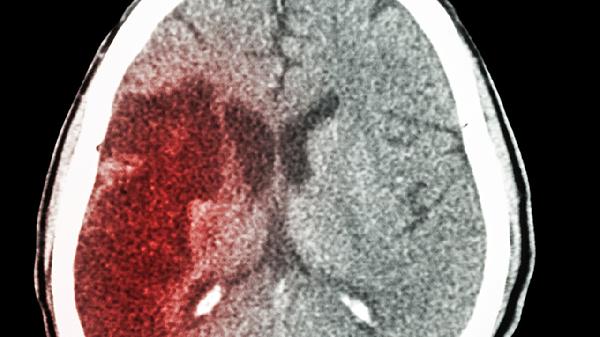

头部摔伤后脑出血的严重程度取决于出血量和部位,可通过保持安静、药物治疗、手术干预、康复训练、定期复查等方式处理。脑出血通常由外伤性血管破裂、高血压血管病变、凝血功能障碍、脑血管畸形、肿瘤侵蚀血管等原因引起。

血肿量超过30毫升或中线移位需行开颅血肿清除术,脑室出血可行侧脑室穿刺引流。手术时机建议在出血后6-24小时,术中需注意保护功能区脑组织。

出院后每月复查头颅CT观察吸收情况,3个月评估格拉斯哥预后评分。长期随访注意迟发性脑积水或外伤性癫痫,遗留功能障碍需持续康复治疗。